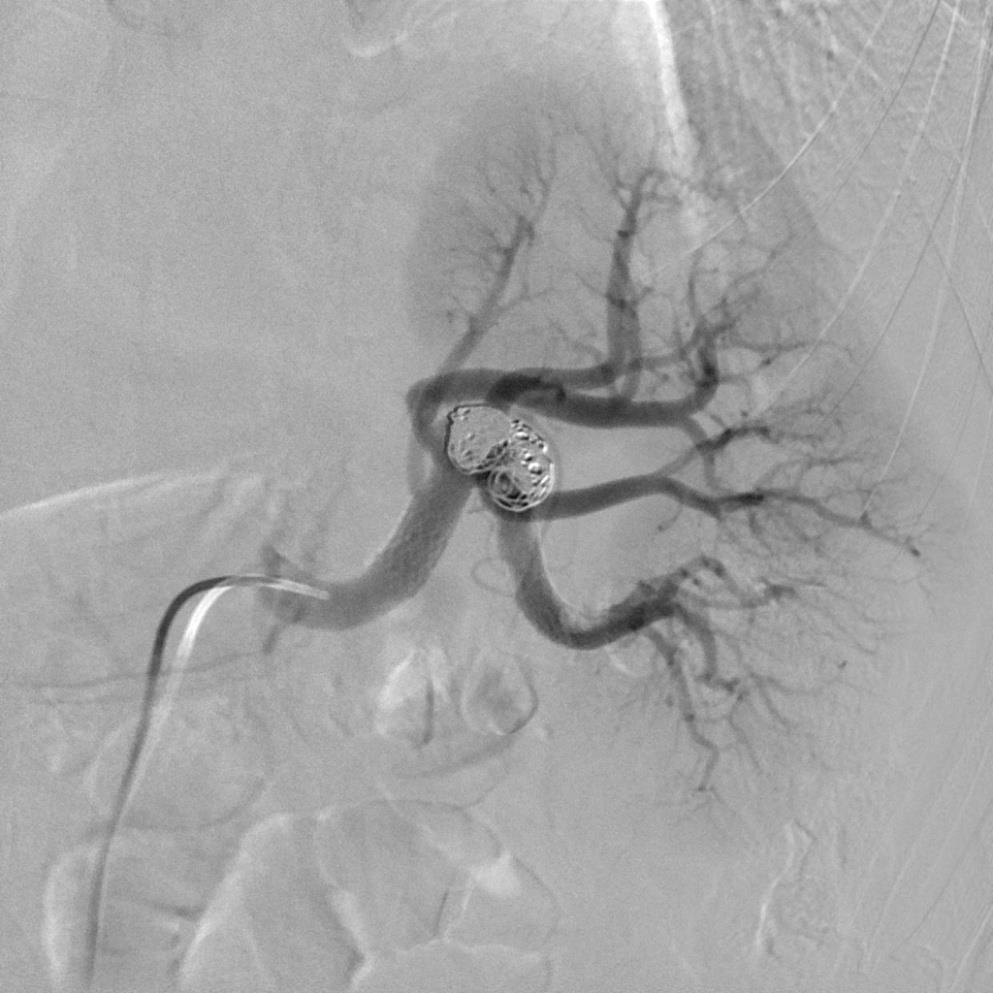

血管造影显示瘤囊,但瘤颈不清楚,似有瘤囊上分支 不能清晰显示瘤颈考虑进行支撑架辅助瘤囊弹簧栓子填塞。支撑架植入后情形

微导管经支撑架网眼进入瘤囊,并造影证实 弹簧栓子开始释放,考虑到瘤囊较大,开始释放弹簧栓子时可以选择较长的弹簧栓子如50cm长

释放弹簧栓子的同时间断造影,以确保弹簧栓子没有进入载瘤动脉 弹簧栓子逸出到载瘤动脉时,可以轻易地回收再重新释放

释放完成后造影显示载瘤动脉远端内血栓。 泵入肝素一天后复查造影,血栓消失。与术前比较少了一支肾后段的动脉。